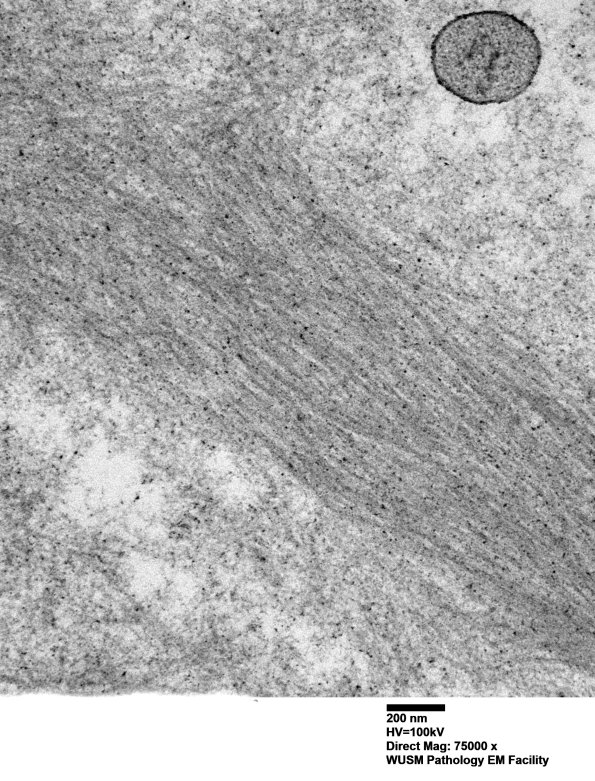

Additional amyloid aggregates seen at multiple magnifications. (electron micrographs)